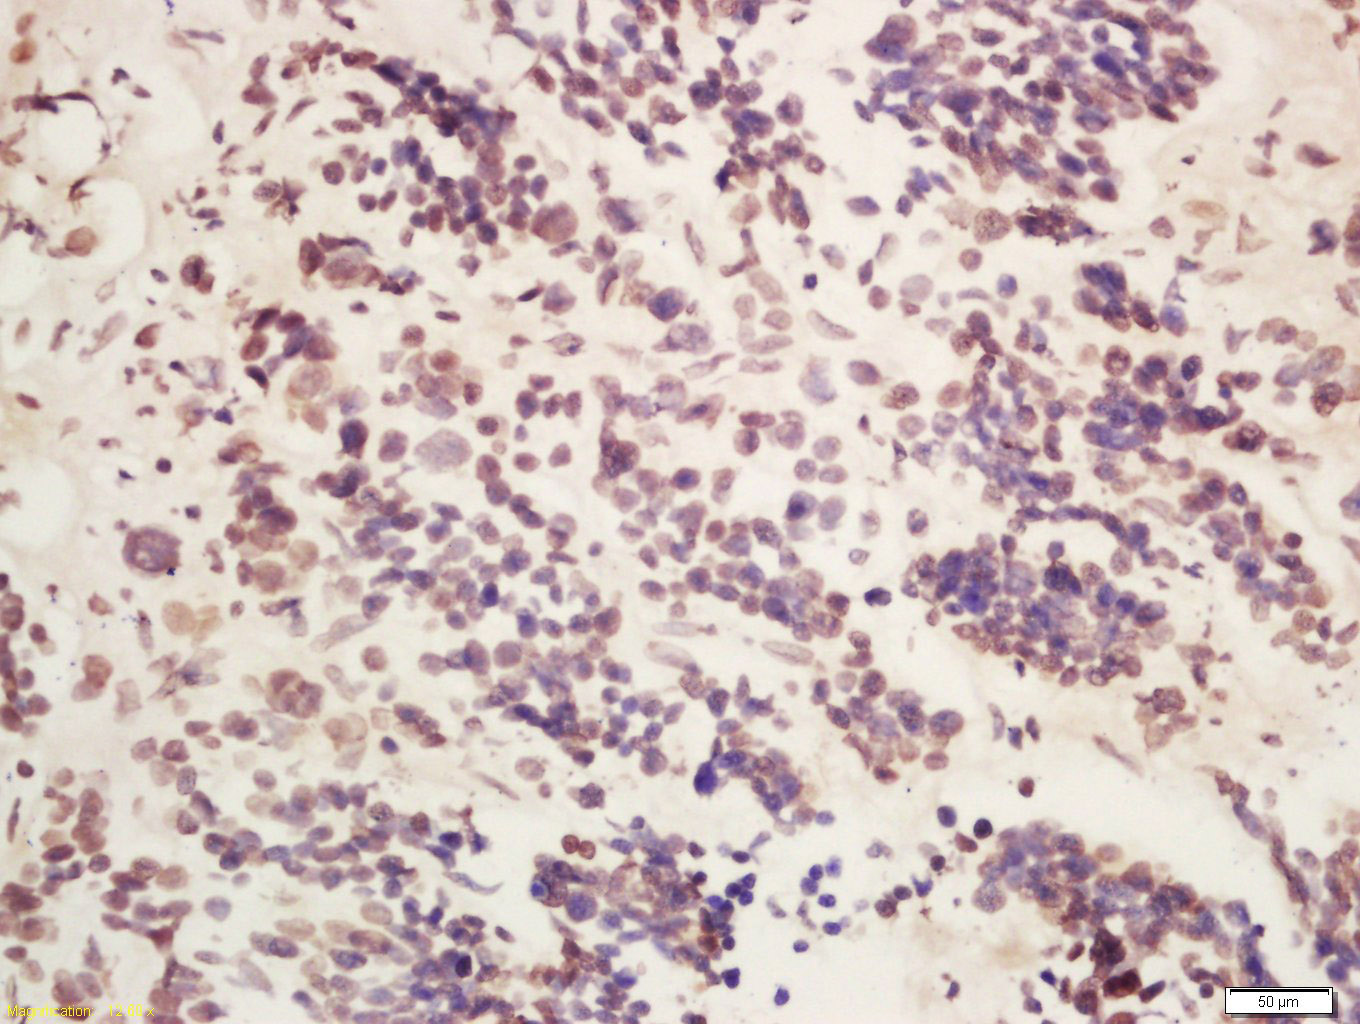

Tissue/cell: human laryngocarcinoma; 4% Paraformaldehyde-fixed and paraffin-embedded; Antigen retrieval: citrate buffer ( 0.01M, pH 6.0 ), Boiling bathing for 15min; Block endogenous peroxidase by 3% Hydrogen peroxide for 30min; Blocking buffer (normal goat serum,C-0005) at 37℃ for 20 min; Incubation: Anti-METTL14 Polyclonal Antibody, Unconjugated(bs-17608R) 1:200, overnight at 4°C, followed by conjugation to the secondary antibody(SP-0023) and DAB(C-0010) staining